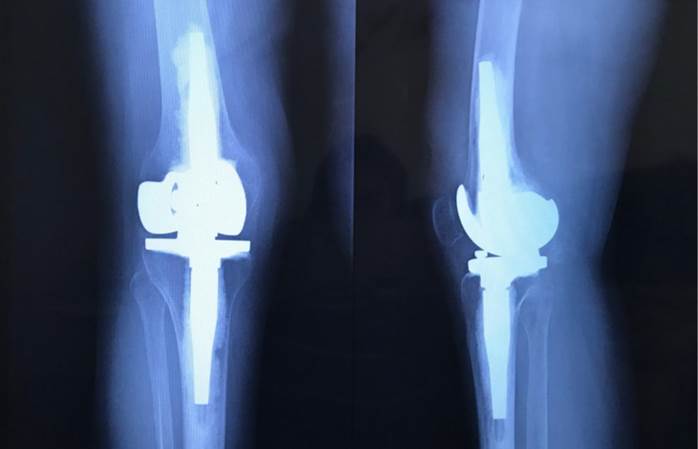

The quasi-invariant flexion position of the knee joint of 9 ° during the initial contact, load response, the middle and terminal support, corresponds to the articular evaluation of the passive range of motion of the knee, the limit of which is - 9 °. It can also be observed that the sagittal view of the postsurgical x-ray (Figure 2) shows a prosthesis in full extension while the position of the joint does not correspond to it but does correspond to a 9 ° knee flexion. This could be due to the technical challenge posed by TKA in patients with polio sequelae in whom, as previously mentioned, joint and metaphyseal deformities, increased external tibial rotation, excessive valgus, poor bone quality, genu-recurvatum and ligament laxity, characteristics that can alter the intrinsic processes of the surgery, such as the making of the canals for the tibial and femoral stems (1-2). In addition, the proper placement of these stems and the setting of the cement, which, being osteopenic bones, can easily generate unwanted alterations in the alignment of the prosthetic element (8).